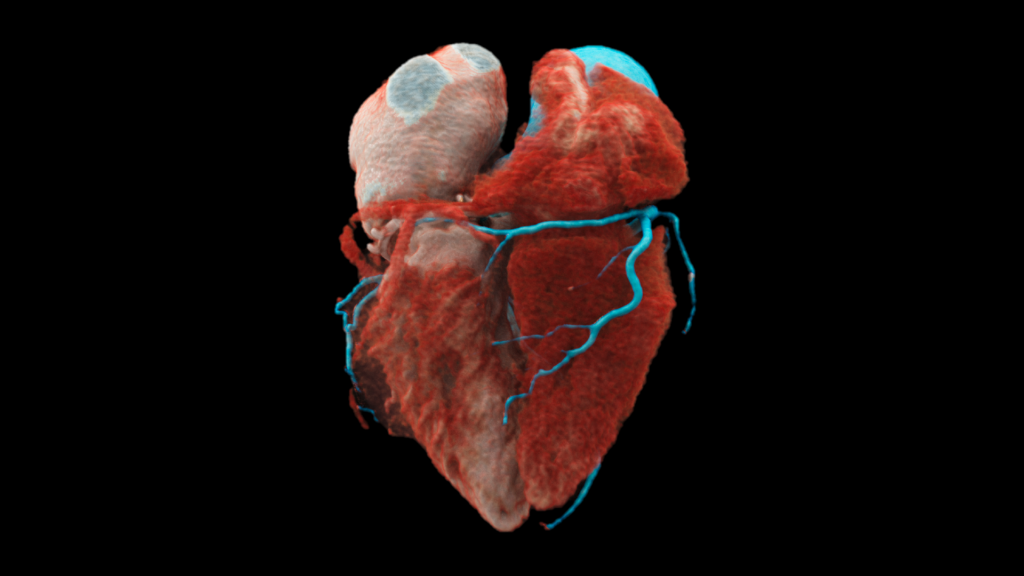

Photon-counting CT cardiovascolare

L’imaging spettrale intrinseco è in grado di visualizzare dettagli sorprendenti in strutture di piccole dimensioni, rendendo possibile il trattamento di un numero maggiore di pazienti, compresi quelli con un valore elevato di calcificazioni o presenza di stent delle arterie coronarie.